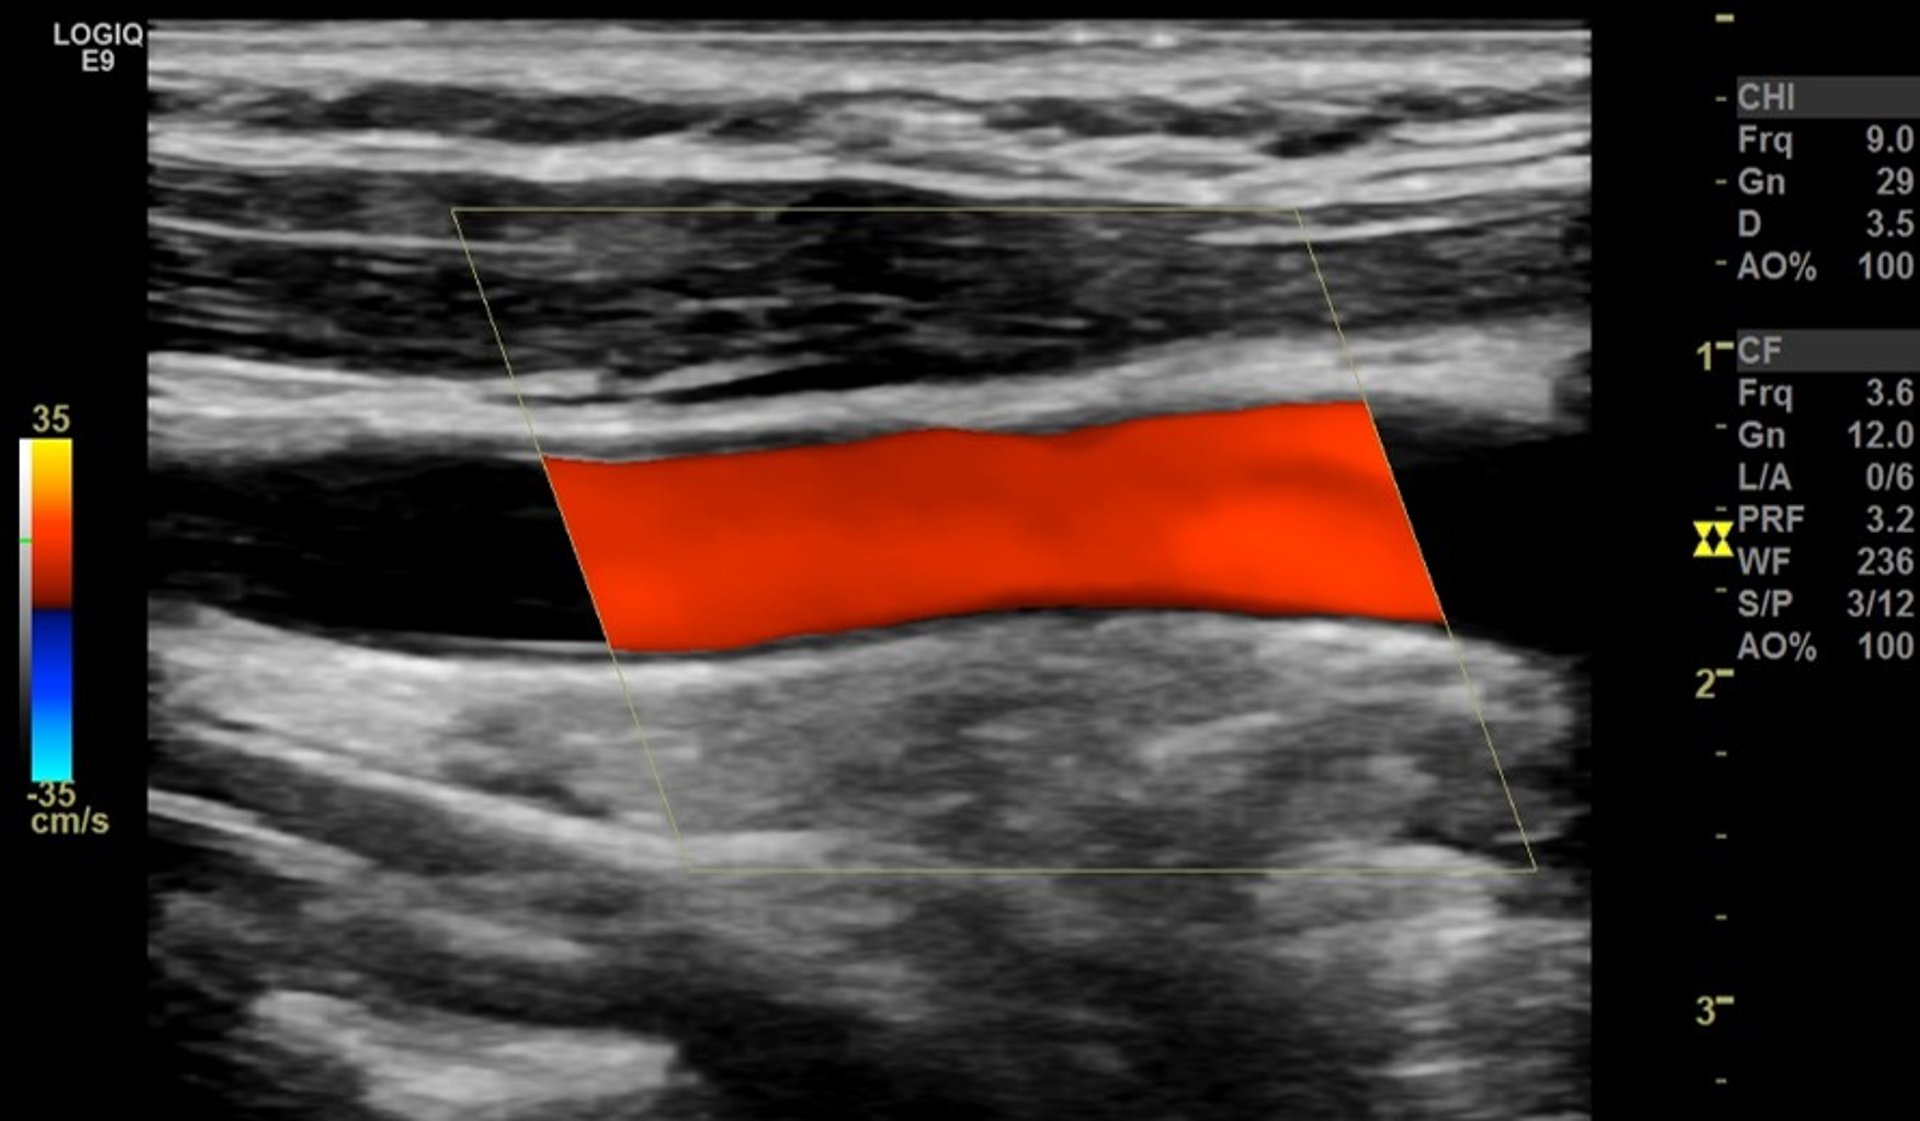

Цветовое доплеровское картирование сонной артерии

Красная полоска соответствует нормальному беспрепятственному кровотоку через крупную артерию в области шеи (общую сонную артерию), вид сбоку.

Изображение предоставлено д-ром Мустафой Мафраджи (Mustafa Mafraji)